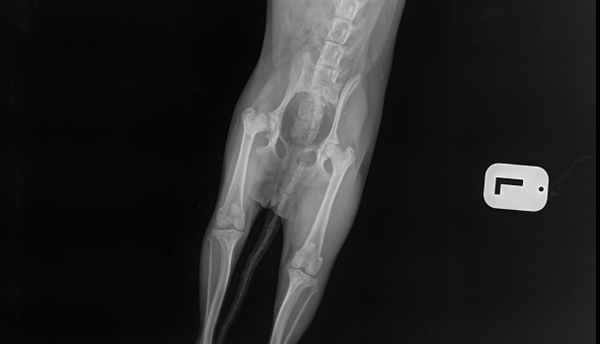

Рентгенограмма собаки с болезнью Легга-Пертеса до операции и после выполненной резекционной (отсекающей) артропластики